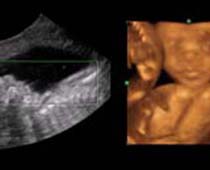

- Les Photos d'Ultrasons du visage du fétus

- 3D Photos échographie du profile du fœtus

- Les avantages cliniques de l'échographie 3D et 4D

- Définition et les Caractéristiques de Quatre Ultrasons Dimensionnels